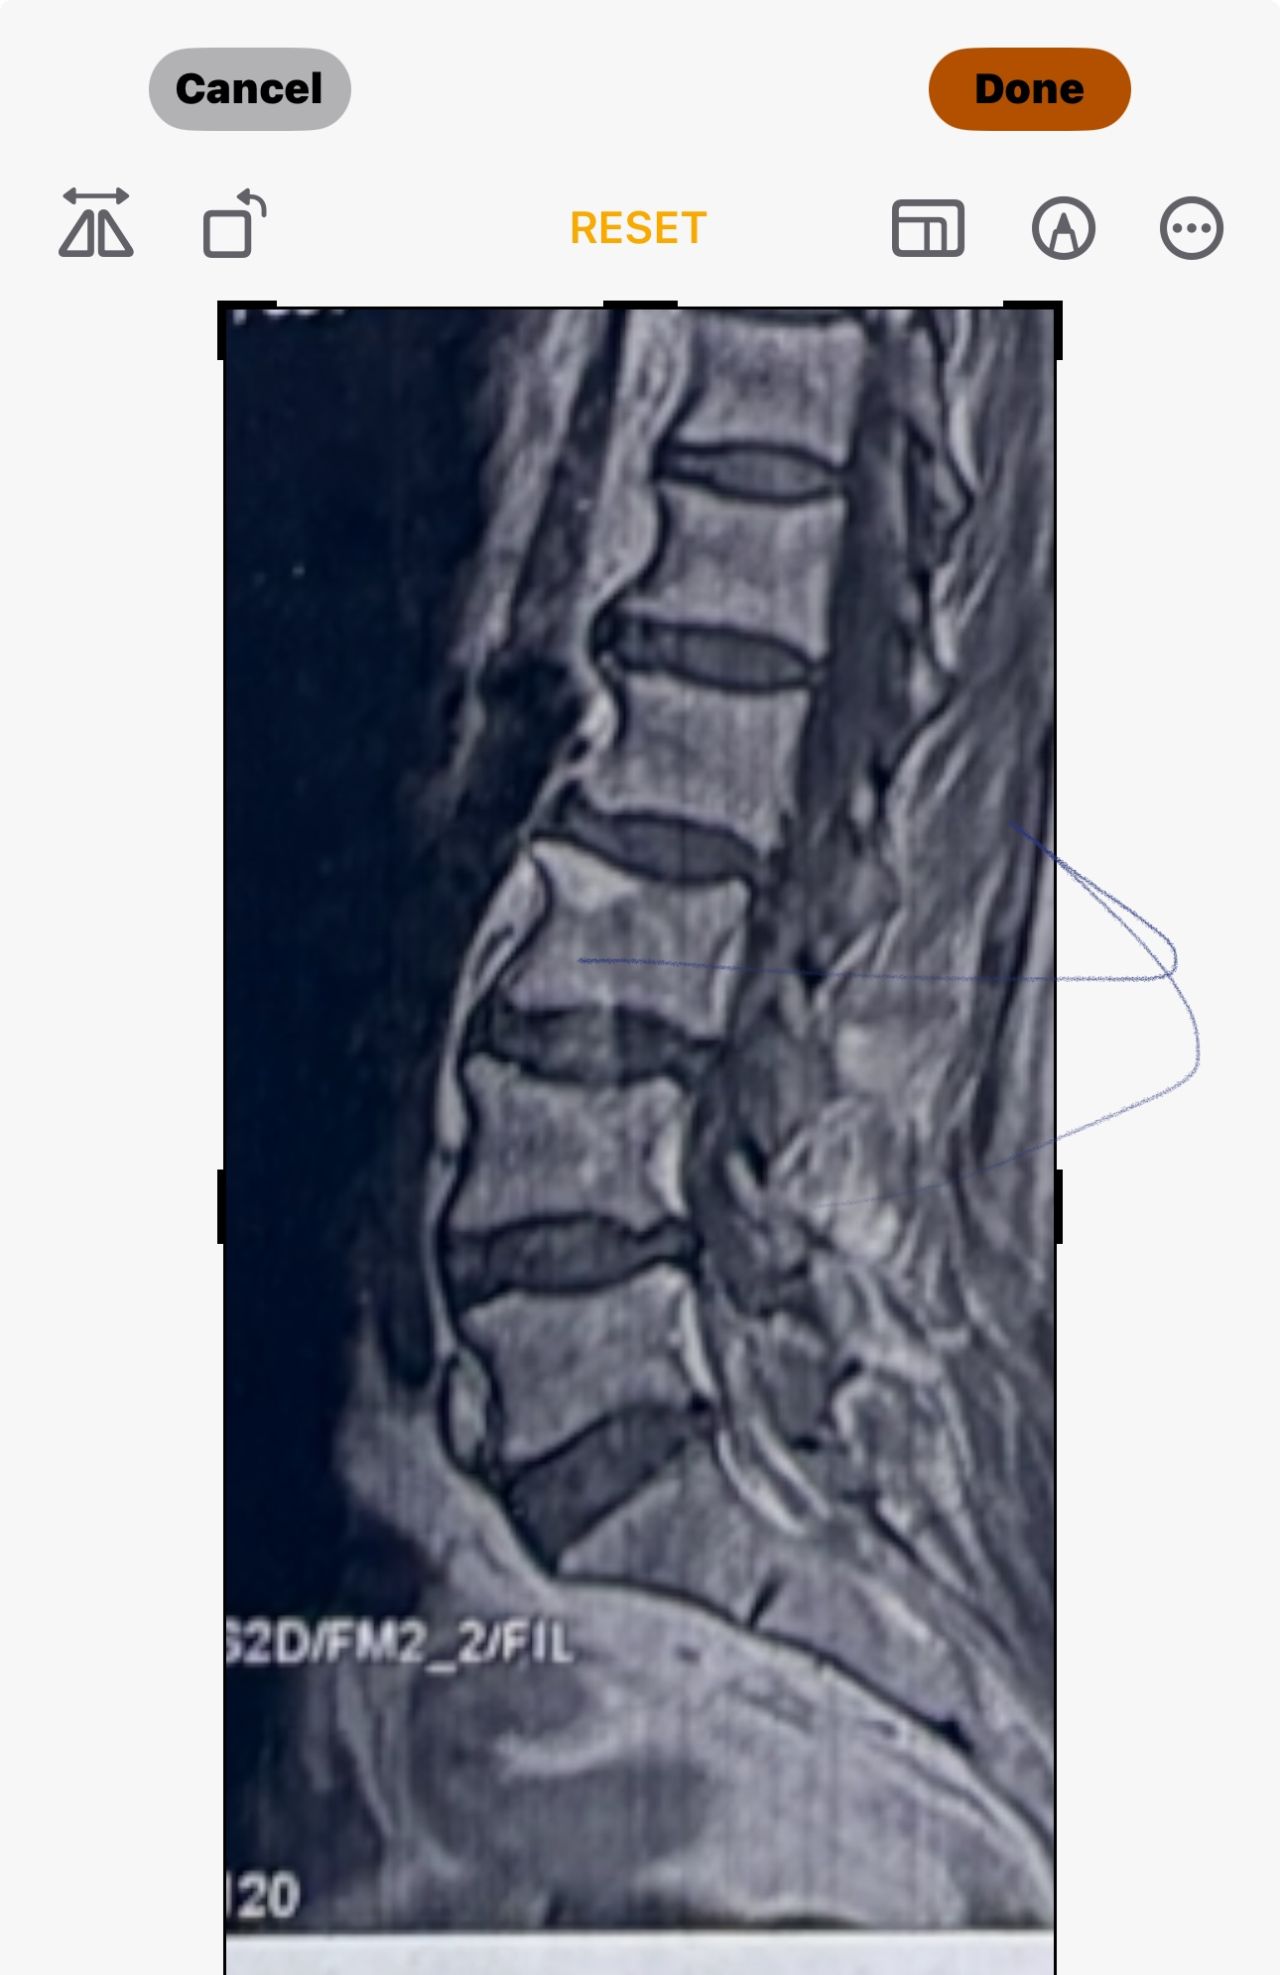

L4-L5 level:

sever L4-5 canal stenosis mainly due to FL hypertrophy?

CSF block. Mild L3 retrolisthesis, facets hypertrophy bilateraly causing L and R IVF stenosis, disc hyperbule

Since I’ve noticed instability in some segments I asked for dynamic L/S x ray:we see mild L4 ant listens due to DjD/DDD. There is not any pars defect.

In cervical mri I marked some findings plus their reports

I will give her treatment via Cox chiropractic flex dis and axial decompression. I would use DTS decompression

Since there is a few mild to moderate DjDs/ DDs in her lower back I won’t use lumbar adjustment on her